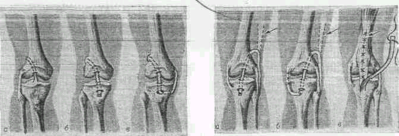

Рис 1.1. Операции на коленном суставе

Рис 1.2. Схема пластики крестообразных и боковых связок